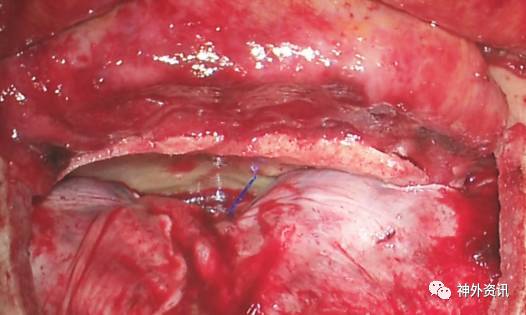

图10. 利用吸引器对额叶实现动态牵拉。将嗅球进行锐性分离,暴露硬膜外扩展的肿瘤前部(星形)。术中图像展示的是一侵犯鼻腔的前颅底软骨肉瘤切除术(上文图1)。锐性分离嗅球直接造成硬膜敞开并且显露肿瘤的硬膜内部分。